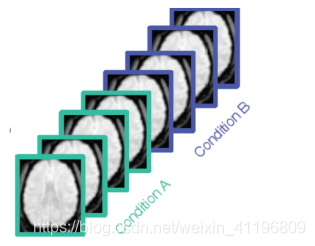

功能图像(Functional (T2*) images)的时间分辨率相对很高。通过它我们可以研究不同时间段里大脑发生了什么变化,例如在这里有两个情况下扫描得到的“大脑功能图像序列”,情况A是用指头敲击,情况B是静息状态。这样我们就可以分析两种状态相比之下大脑的信号有什么区别。但其空间分辨率较低,相对结构图像来说很模糊。